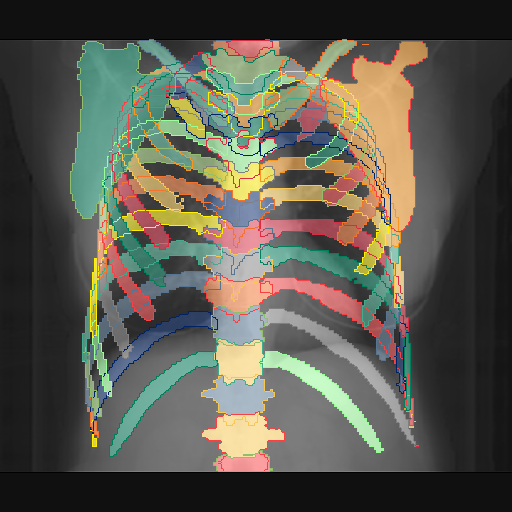

We show qualitative results for frontal projections in Fig. 2. We show a subset of classes belonging to the supercategories lungs, vascular systems, bones, and abdomen/digestive system. The predictions show minor deviations at the boundaries of the individual classes of the respiratory and vasculature system, while some inaccuracies become visible in the abdominal area. The qualitative results for the lateral projections are displayed in Fig. 2. Akin to the frontal view, the predictions show smoother borders but align with the ground truth. Apart from this, the segmentations provide matching insights on the thoracic anatomy with a slight deviation from the ground truth for both frontal and lateral views.

Fig. 2 shows quantitative segmentation results for frontal (top row) and lateral (bottom row) views. We display the class performances in the form of IoU (left), DICE (center), and Hausdorff distance (right) for each sample as a scatter plot with the mean performance for the classes shown by a line plot. Generally, we see performances for standard spinal classes, such as the thoracic vertebrae with average IoU-scores above 80%, while the average performance of rare vertebrae of the dataset belonging to the cervical and lumbar spine can drop down to 40%. In the frontal view, there exists more variance in thoracic vertebrae segmentation performance compared to the lateral view. Bone structures such as the sternum, clavicles, and scapula achieve IoUs in the mean from 85% to 95%. For ribs, we can see a noticeable performance drop for the anterior parts of the lower ribs independent of the side. The lower anterior ribs typically do not contain a large area, making them difficult to segment. This behavior is mirrored in the lateral view across the metrics. Abdominal classes can vary in segmentation quality as they occur in a nearly homogenous region. For example, while the liver or stomach are typically well-segmented, the duodenum and kidneys are more complex. Heart and Lung related classes show near-perfect segmentations with scores above 90% IoU. Breast tissue segmentation in comparison only achieves a mean of 70% mIoU. It can be noted that classes in the lateral view tend to have slightly better scores than their frontal counterparts.